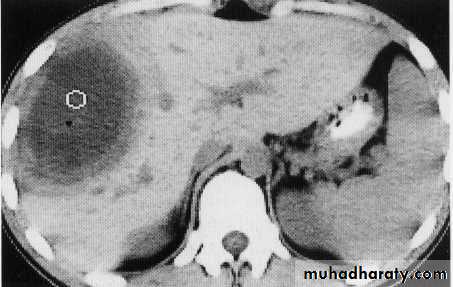

hemangeoma